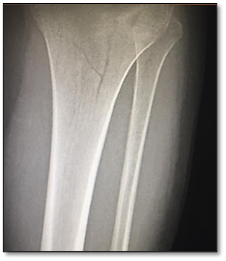

Exámenes de imagen

Radiografía de Rodilla izquierda (imagen 1)

Imagen 1. Fractura de fractura de la meseta tibial

Se TAC la cual reporta fractura de la meseta tibial lateral con extensión cortical posterior, siendo un patrón concordante con fractura de Schatzker tipo V.